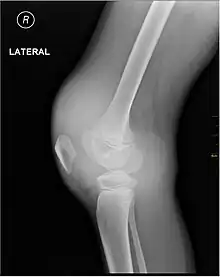

- X-ray of Hemarthrosis